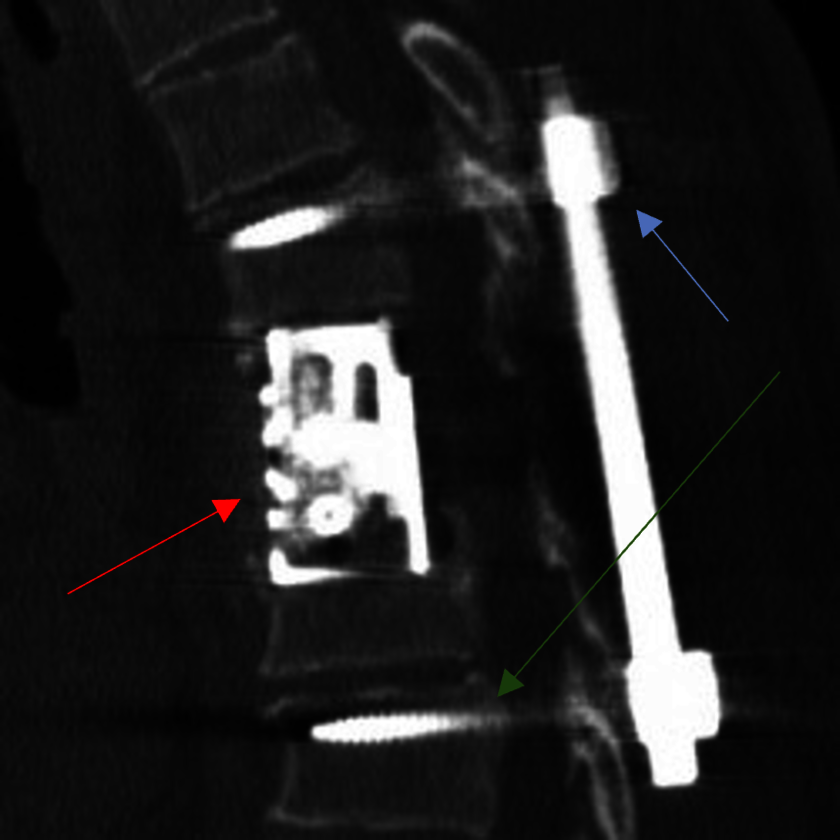

Abbildung 2: Bei metastatischen Prozessen im Bereich der Brustwirbelsäule kann es sinnvoll sein, sowohl den Tumor im vorderen Abschnitt der Wirbelsäule zu entfernen und einen Platzhalter (Cage) einzusetzen (roter Pfeil).

Besonders kritisch bei diesen Operationen ist die Bewahrung der Rückenmarksfunktion. Bei sehr deutlichen Befunden sollte durch kontinuierliche Überwachung dieser Rückenmarksfunktionen durch Strommessungen (Monitoring) während der Operation effektiv eine Verschlechterung vermieden werden. Der Einsatz dieser Monitoringverfahren und die Verwendung minimalinvasiver Techniken erlauben meist eine großzügige, wann immer möglich vollständige Tumorentfernung ohne operationsbedingte Funktionseinbußen. Zudem ist die schnelle Wundheilung zur möglichst raschen postoperativen Genesung bei diesen Patientinnen und Patienten besonders kritisch, da hier zügig im Nachgang Therapieverfahren wie z.B. Chemotherapie und/ oder Bestrahlung (wieder) gestartet werden müssen. In diesem Zusammenhang ist es besonders notwendig, immer die minimalste sinnvolle OP-Methode einzusetzen. Hierbei sind Möglichkeiten durch das Einsetzen von Roboter-assistierten OP-Verfahren sehr sinnvoll.